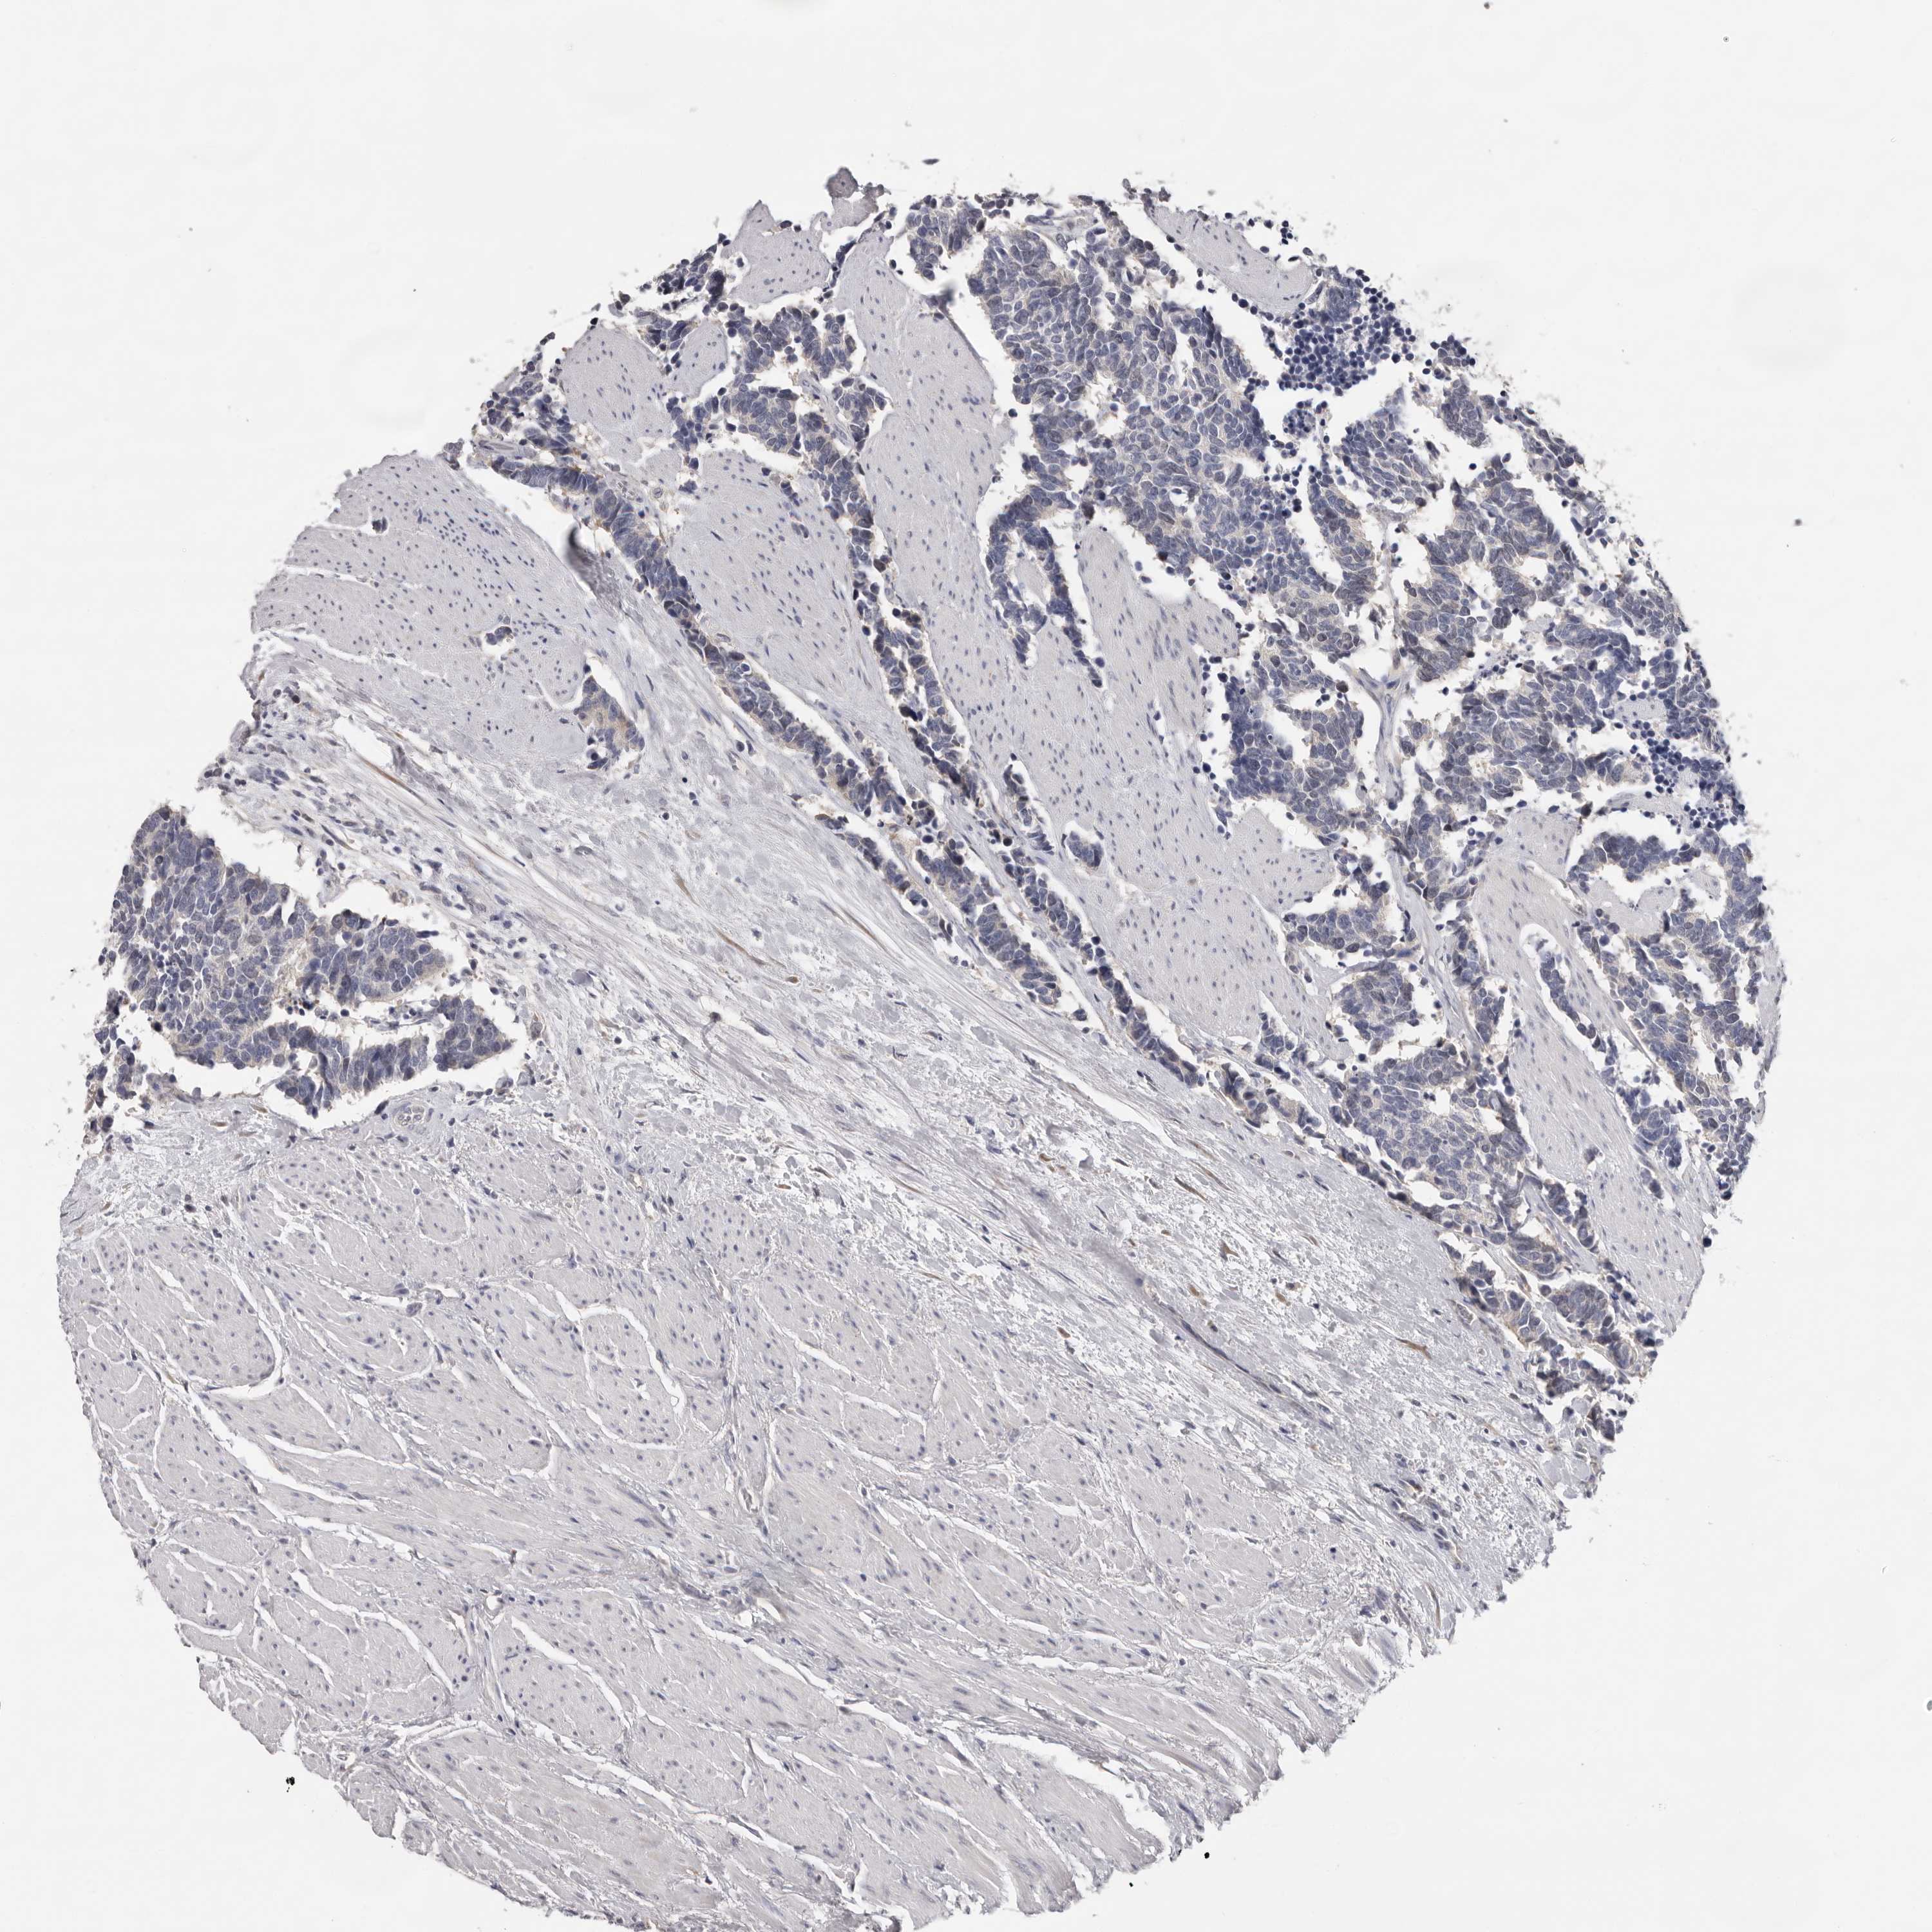

CARCINOID - Protein expressioni

A mouse-over function shows sample information and annotation data. Click on an image to view it in a full screen mode. Samples can be filtered based on level of antibody staining by selecting one or several of the following categories: high, medium, low and not detected. The assay and annotation is described here.

Antibody stainingi

Antibody staining in the annotated cell types in the current human tissue is reported as not detected, low, medium, or high, based on conventional immunohistochemistry profiling in selected tissues. This score is based on the combination of the staining intensity and fraction of stained cells.

Each image is clickable and will lead to virtual microscopy that enables deeper exploration of all samples and also displays staining intensity scores, fraction scores and subcellular localization as well as patient and tissue information for each sample.

Antibody HPA023081

Carcinoid, malignant, NOS